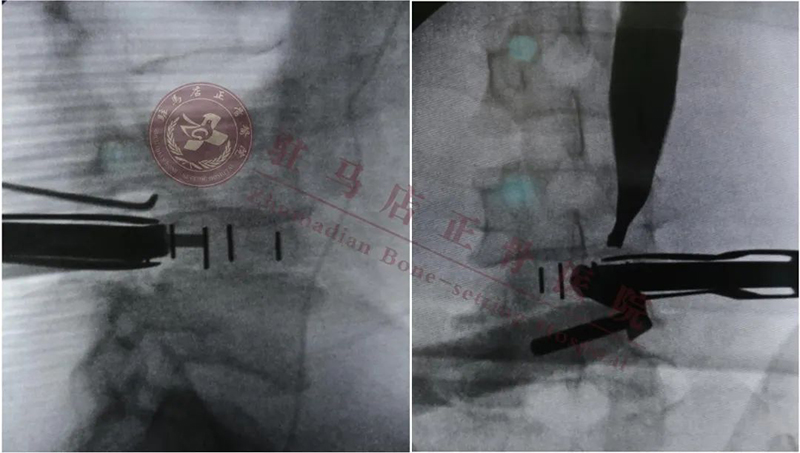

cage横打的位置